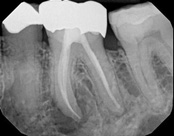

In this situation, some would say the canals are so “calcified” that root canal treatment can’t be done; or sometimes the canal can’t be found. And because of that the tooth would need an extraction and an implant. In some instances, root canal therapy can’t be done but that does not mean the tooth is a loss. The solution is micro-apical surgery, an apicoectomy.